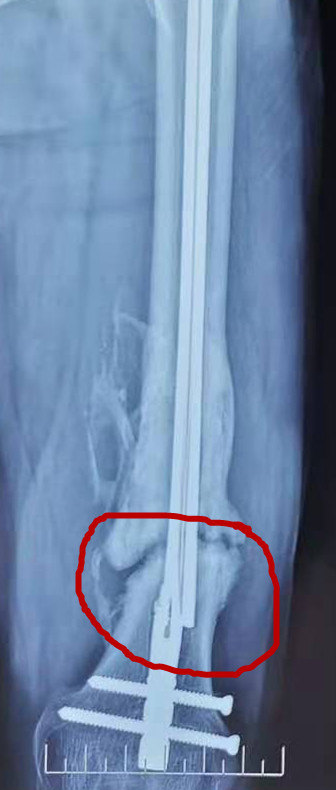

问 本人性别男,今年30岁, 请问我右脚小拇指骨折错位了 需不需要做手术啊 所患疾病:骨折并错位(已到医院就诊) 答 脚的小拇指骨折错位,具体什么情况,需不需要手术,需要看到片子才能确定。 11

小指骨折手术-手指骨折的第一个迹象就是疼痛。 疼痛程度取决于骨折的严重程度。 手指受伤后要小心触碰它,并密切留意疼痛程度。 1 你很难立刻确认手指是否骨折,因为脱臼和扭伤一样会引起急性疼痛和触痛。骨折愈合时间一般恢复期为6个月,我们现在重点讨论一下常见骨折部位的愈合时间。 当然这个时间是指骨折断端愈合,但没有达到骨折临床症状消失的时间。 具体如下: 头部骨折 上下颌骨要60~1